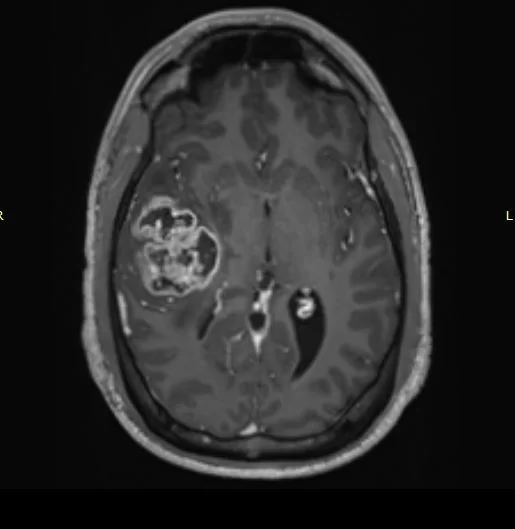

Αφαίρεση γλοιώματος σε κρίσιμη (λειτουργική – eloquent) περιοχή με την ασθενή ξύπνια

Ασθενής 45 ετών η οποία παρουσίασε αιμωδίες (μουδιάσματα) στη δεξιά πλευρά του σώματος και ακολούθως επιληπτικές κρίσεις. Ο έλεγχος με μαγνητική έδειξε όγκο στο αριστερό